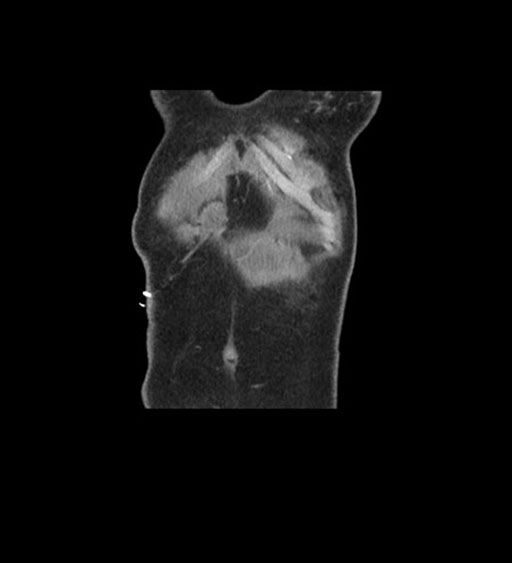

Coronal Arterial

Coronal Venous